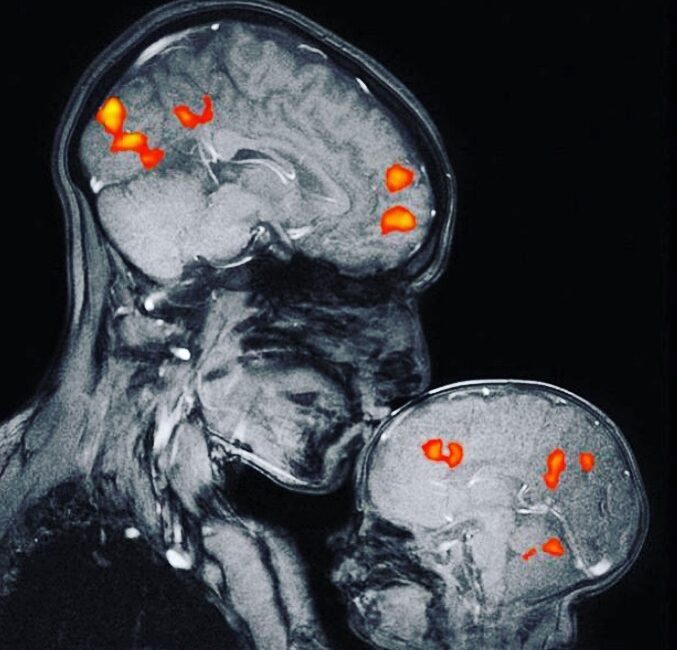

Моментот кога се случува бакнежот, мозокот на бебето станува помазен и потемен, а до тоа доаѓа затоа што има значително помалку бела материја. Активирањето на фотографијата не се однесува на чинот на бакнувањето, туку на организацијата на функционални активности во мозокот на бебето. Бакнувањето во вашиот мозок предизвикува хемиска реакција и го зголемува лачењето на хормонот окситоцин. Овој хормон честопати се нарекува хормон на љубовта, бидејќи го зајакнува чувството на приврзаност и наклонетост. Бакнувањето го активира системот за наградување во мозокот, лачејќи допамин, кој прави да се чувствуваме подобро. Исто така, се ослободува вазопресин, кој мајките ги поврзува подлабоко со бебињата и партнерите, но и серотонин, кој помага во регулирањето на нашето расположение.

Мајката и бебето на фотографијата се заедно во магнетната резонанција. Да, машината произведува звуци што се вознемирувачки и за возрасен човек. Бебето имало слушалки, исто како и мајката. Снимката не била направена веднаш, туку имало неколку обиди. Кога бебето конечно заспало на градите на мајката, било снимено што се случува во неговата глава додека мајката го бакнува.

– Во мојата лабораторија користиме магнетна резонанција за да го следиме протокот на крв низ мозокот на детето. Им читаме приказни и набљудуваме како се менува активноста на мозокот во зависност од текот на приказната. На тој начин истражуваме што мислат децата за мислите на другите луѓе. Оваа снимка не е направена за дијагностички или научни цели. Мислам дека никој досега не направил магнетна резонанција на мајка и бебе. Го направивме тоа затоа што сакавме да видиме. На некои луѓе оваа снимка им е вознемирувачки потсетник за тоа колку е ранлив човекот. На другите им е фасцинантно како две личности, со невидлива гардероба, коса и лице, станаа универзални и може да бидат кои било мајка и бебе, на кое било место или историски период. Другите беа воодушевени од тоа колку е различен мозокот на бебето од мајчиниот – помал е, помек и потемен бидејќи има помалку бела материја. И еве еден од најголемите проблеми во невронауката – како промените во тој специфичен мал орган ќе помогнат во разоткривањето на човечкиот ум? Мајката и детето се моќен симбол на љубовта и невиноста, убавината и плодноста. Иако се почитуваат овие мајчински вредности и жените што ги претставуваат, тие обично се сметаат за спротивности на другите вредности: интелект, напредок и моќ. Но, јас се занимавам со невронаука и работев за да ја направам оваа слика. Исто така, јас сум и мајката на сликата, заедно со мојот мал син – напишала научникот Ребека Сакс.